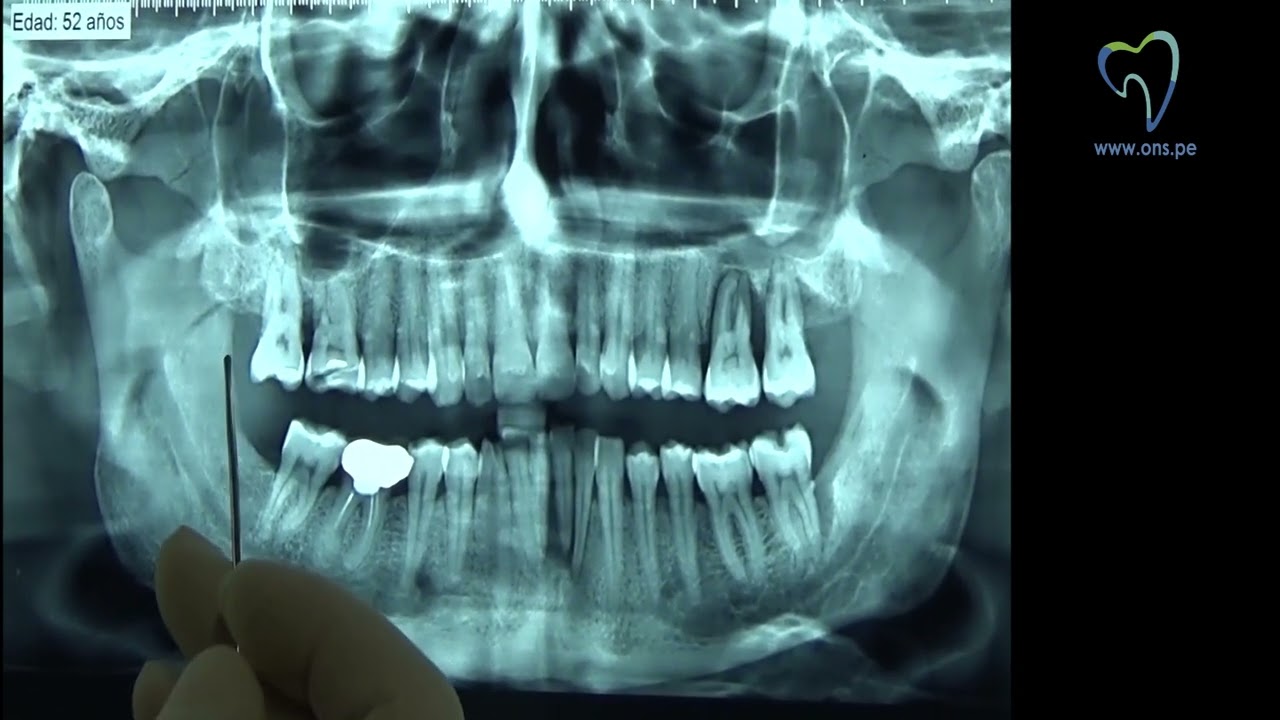

Anatomia em radiografia panorâmica YouTube

Anatomia em radiografia panorâmica YouTube Dim Radiografia Panoramica L’ ortopantomografia, comunemente chiamata panoramica dentale, è una tecnica radiografica avanzata che offre una visione completa della. Tipos de radiografías que realizamos sin turno previo en dim rivadavia de lunes a viernes de 07:00 a 23:00 hs, sábados y domingos de 07:00. La radiografía panorámica es una técnica radiológica que muestra las estructuras óseas (los maxilares, la articulación de la.. Dim Radiografia Panoramica.